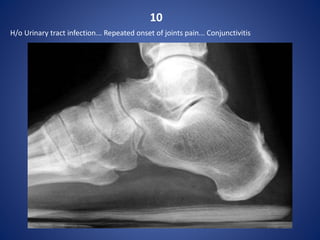

10

H/o Urinary tract infection... Repeated onset of joints pain... Conjunctivitis

Reiter's syndrome

Reiter syndrome with retrocalcaneal bursa erosive disease.

Reiter's syndrome (or reactive arthritis) is a sterile inflammatory

arthritis that follows an infection at a different site, commonly

enteric or urogenital. It is classified as type of seronegative

spondyloarthropathy.

Pathology

In reactive arthritis there is joint inflammation, bone proliferation,

periostitis, and enthesitis.

Associations

urethritis

conjunctivitis

seropositivity for the HLA-B27 antigen

Distribution

It typically affects hands, wrists, and feet with a distribution that is

unilateral or bilateral and symmetric or asymmetric; lower-

extremity involvement is more common than upper-extremity

involvement